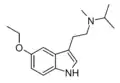

| Chemical structure | Short Name | Origin | Ring Substitution | RN1 | RN2 | Full Name | CAS Number |

|---|---|---|---|---|---|---|---|

| MiPT | artificial | H | CH3 | CH(CH3)2 | N-Methyl-N-isopropyltryptamine | 96096-52-5 |

| 5-MeO-MiPT | artificial | 5-OCH3 | CH3 | CH(CH3)2 | 5-methoxy-N,N-methylisopropyltryptamine | 96096-55-8 |

| 5-Ethoxy-MiPT | artificial | 5-OCH2CH3 | CH3 | CH(CH3)2 | 5-ethoxy-N-methyl-N-isopropyltryptamine | |